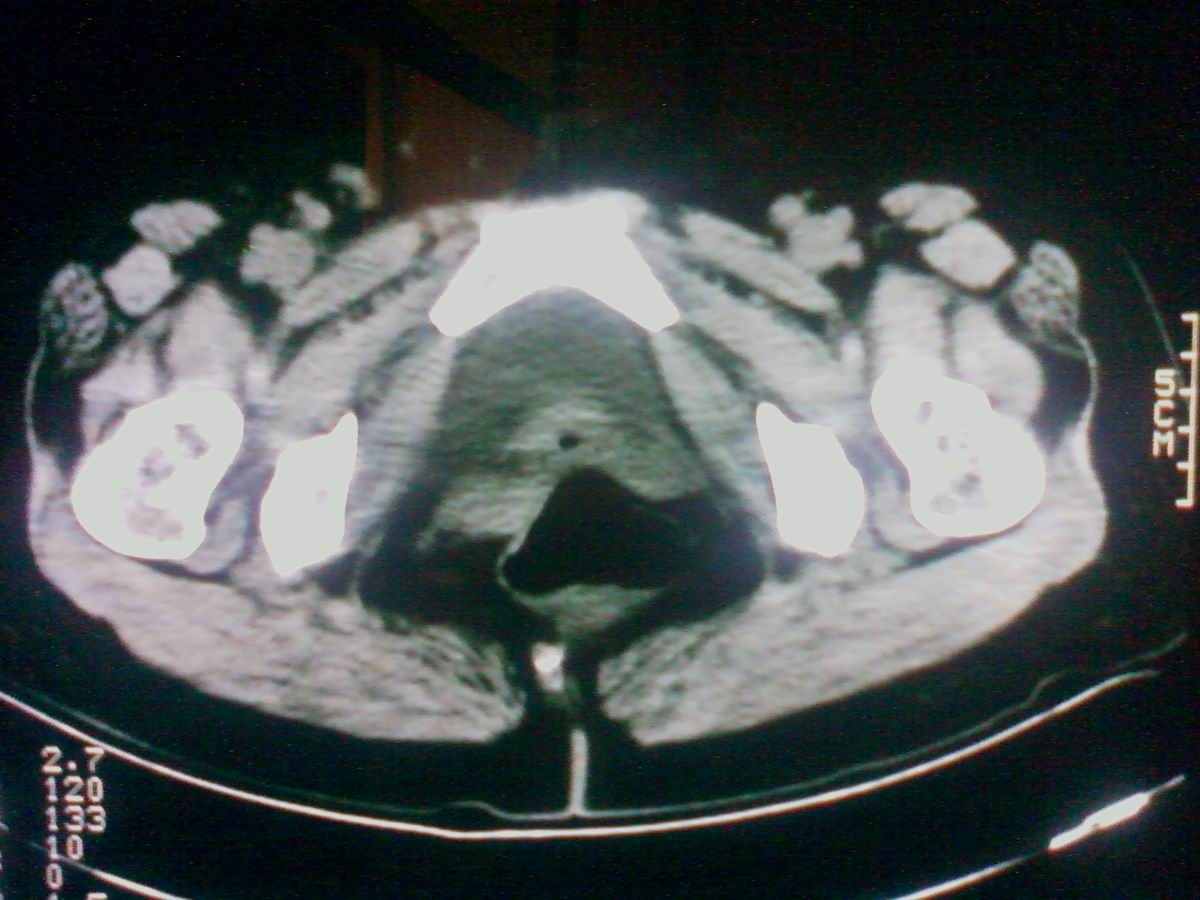

标题: CT25799:女性患者,45岁,腹胀,上腹部疼痛来诊,B超示盆腔 [打印本页]

标题: CT25799:女性患者,45岁,腹胀,上腹部疼痛来诊,B超示盆腔

考虑卵巢癌伴腹水

1)考虑卵巢恶性肿瘤。2)腹水。